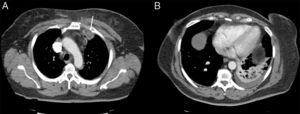

A 60-year-old woman, non-smoker, with no history of immunosuppression or risk factors for lung disease attended the emergency room with pleuritic pain and pain in the left shoulder, 38°C fever, cough without expectoration and intense pain in the mid-clavicular region and left shoulder. Chest radiograph revealed mild infiltrate in the left lower lobe. Signs of consolidation and egophony in the left lower field were detected on examination. A very painful non-fluctuating swelling with no signs of inflammation in the skin was observed in the upper left sternoclavicular region. Fiberoptic bronchoscopy was performed, revealing signs of inflammation, and samples were sent for pathology and microbiology studies. Blood cultures were negative. No valvular lesions or vegetations suggestive of endocarditis were observed on echocardiogram. Empirical treatment with ceftriaxone and levofloxacin was started, with little clinical response, while morphine was required for pain control. Chest computed tomography (CT) showed inflammatory changes in the left pectoral muscle and a pseudonodular image measuring 3.3×2.3cm in the space between the anterior portion of the first and second left costal arch, and pulmonary consolidation with pleural effusion in the left lower lobe (Fig. 1). Findings were confirmed on both ultrasonography of the neck and bone scintigraphy. Ultrasound-guided fine needle aspiration and biopsy was performed, from which S. aureus was isolated. The strain was resistant to ampicillin, and susceptible to erythromycin, gentamicin, clindamycin, ciprofloxacin, levofloxacin, and cotrimoxazole. The same microorganism was isolated from the bronchoscopy samples. During admission, intravenous ciprofloxacin and amoxicillin–clavulanic acid were administered, in line with susceptibility results, and improvement was observed in clinical symptoms, radiological signs, and acute phase reactants. Drainage was not required. Treatment continued on an outpatient basis for another 40 days, with complete resolution of the syndrome.